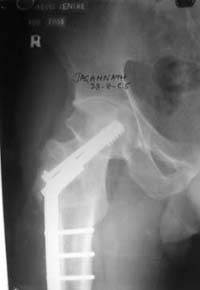

При явно выраженном варусе и флексионных состояниях после сросшихся переломов шейки бедра у молодых рекомендуется реконструктивная операция по исправлению варуса для предотвращения раннего деформирующего артроза, приводящего в результате переднего импинжмента, как показано на снимке.

Межвертельная вальгусная остеотомия представляет наименьший риск среди всех реконструктивных операции в проксимальной части бедра, создавая наилучшие биомеханические условия (увеличивается сила абдукторов, увеличивается сила суставной реакции, уменьшение рычага моментов абдукторов и уменьшение скольжения) и при меньшем риске повреждения кровоснабжения головки, где обычно в 90% случаях достигается отличный результат при применении метода для лечения ложных суставов шейки бедра.

По моему, 120 градусная угловая пластина blade plate решит все проблемы, только необходим предварительный расчет угла остеотомии, и во время фиксации пластины не забыть латерализацию бедра, иначе ось конечности от варуса перейдёт в нежелательный вальгус.

Для предупреждения вальгуса клинок пластины берется на 10-12 мм длиннее чем предварительный туннель на головке, тогда во время

фиксации за бедро пластина автоматически приблизит бедро и происходит латерализация бедра. Если между клинком и латеральным кортексом бедра положить частицу кости от остеотомии тогда образуется дополнительная компрессия на фокусе несращения.

Здесь мои диаграммы для расчета угла остеотомии и латеризации бедра.